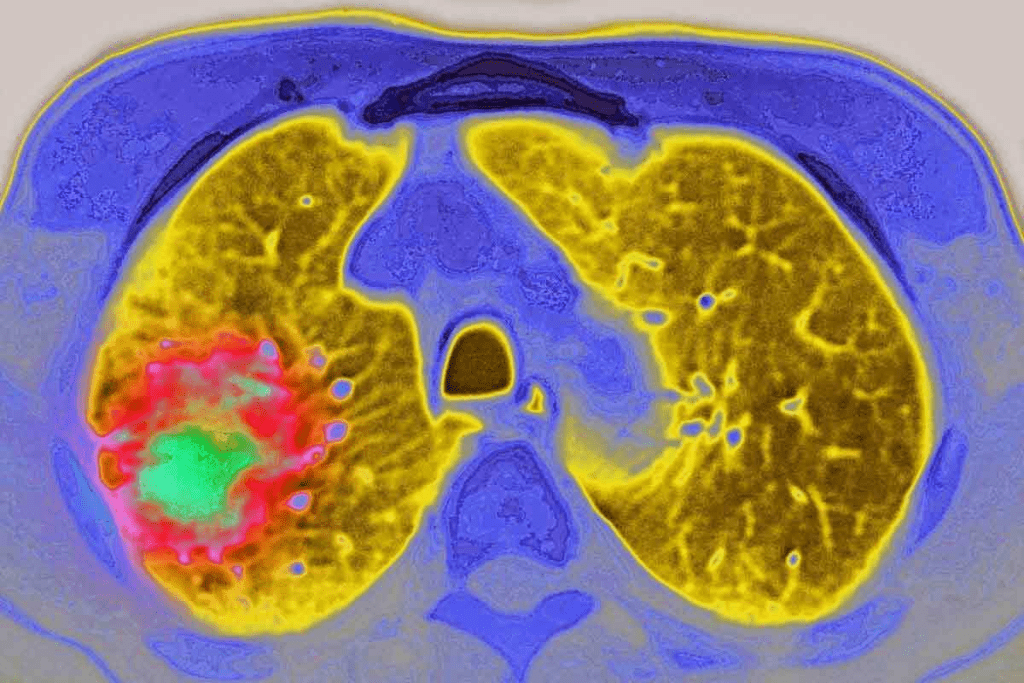

Metastatic Cancer to Bones

Metastatic cancer to bones is more common and occurs when cancer cells from other parts of the body, such as the breast, prostate, or lung, spread to the bone. Bone scans are particularly useful in detecting metastatic bone disease, as they can show areas of increased uptake corresponding to metastatic deposits.

Characteristic Patterns of Cancerous Uptake

Cancerous uptake on bone scans often exhibits characteristic patterns that help in diagnosis. For instance, metastatic disease can cause multiple areas of increased uptake scattered throughout the skeleton. In contrast, primary bone tumors may show a more localized area of uptake. Understanding these patterns is crucial for interpreting bone scan results accurately.